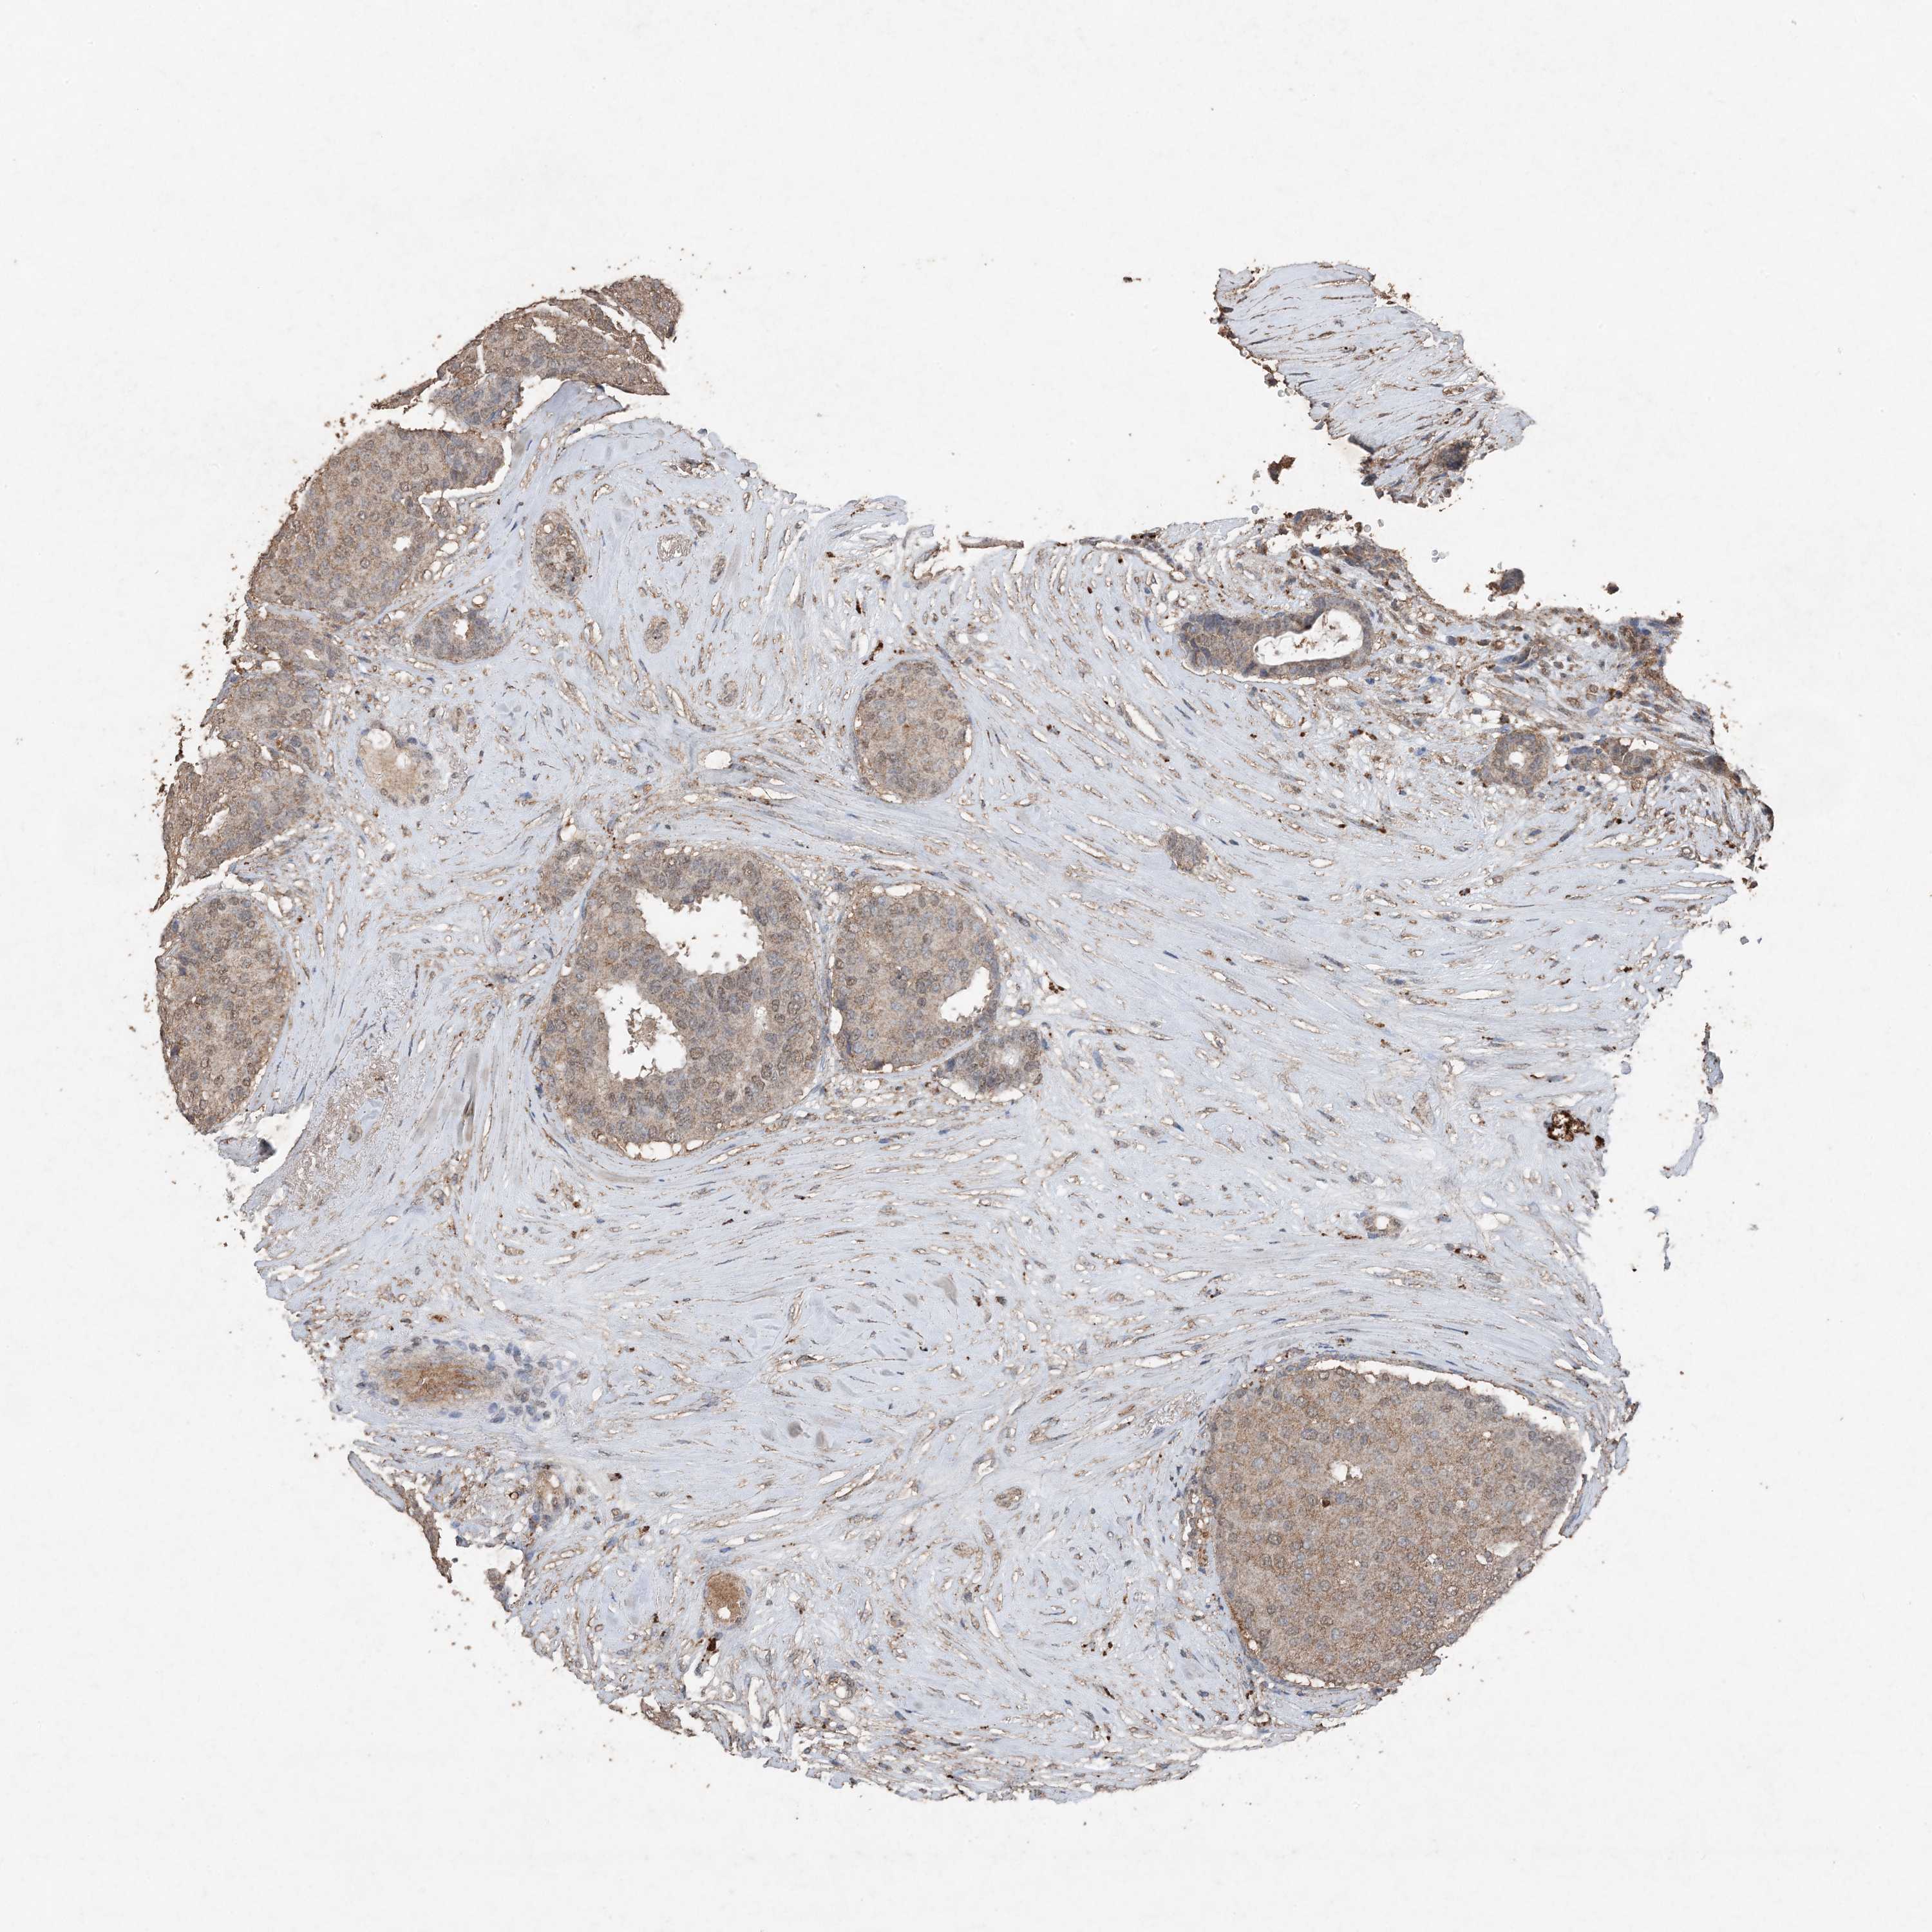

CANCER BREAST CANCER Show tissue menu

BRCA TCGA BRCA VALIDATION PROTEIN EXPRESSION